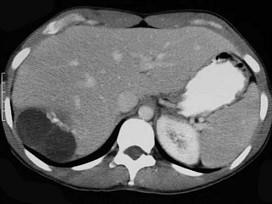

下列诊断肝包虫病的方法,错误的是 ( )A、B超B、补体结合试验C、诊断性穿刺D、间接血凝法试验E、包虫囊液皮内试验(Casoni试验)

问题 下列诊断肝包虫病的方法,错误的是 ( )

选项 A、B超 B、补体结合试验 C、诊断性穿刺 D、间接血凝法试验 E、包虫囊液皮内试验(Casoni试验)

答案 C